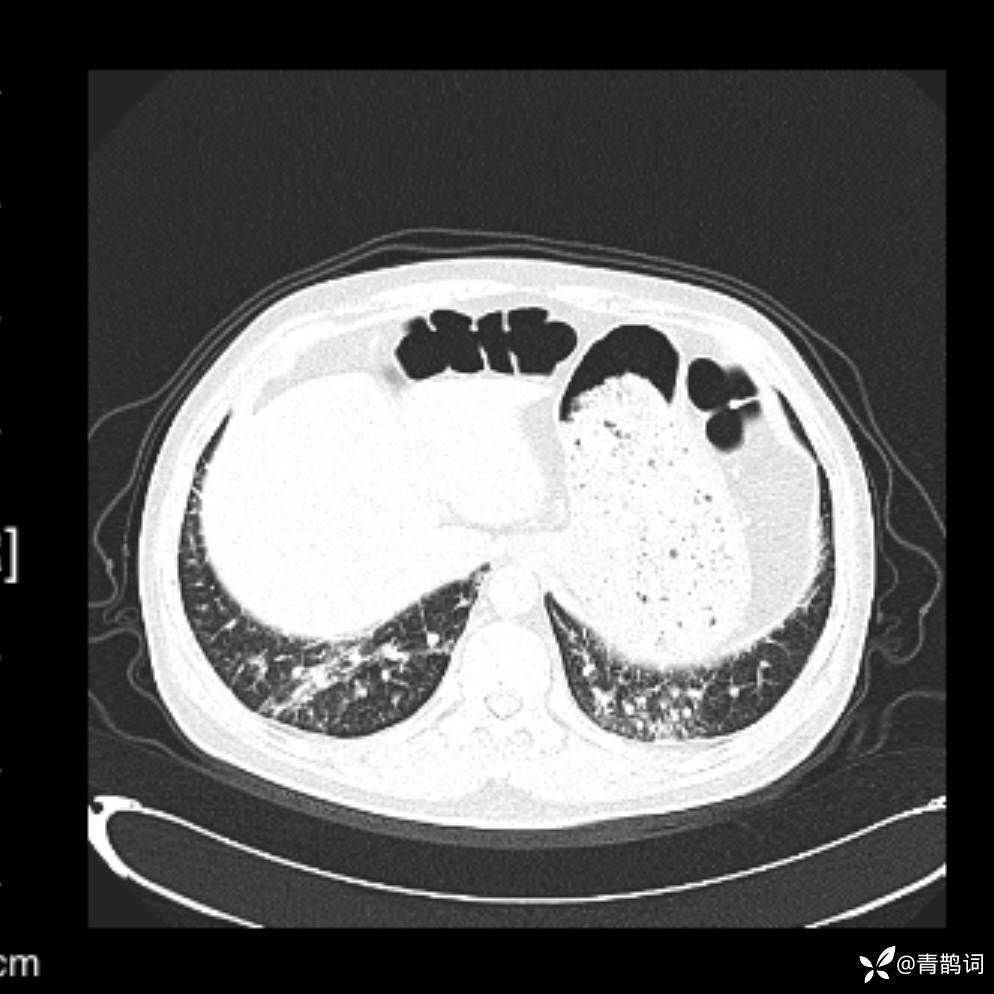

患者年龄:30岁。

患者性别:男。

简要病史:左颜面部肿胀2年,反复咳嗽咳痰,逐渐加重。

辅助检查

结合病史及影像学表现,期待评论区各位老师各抒己见~